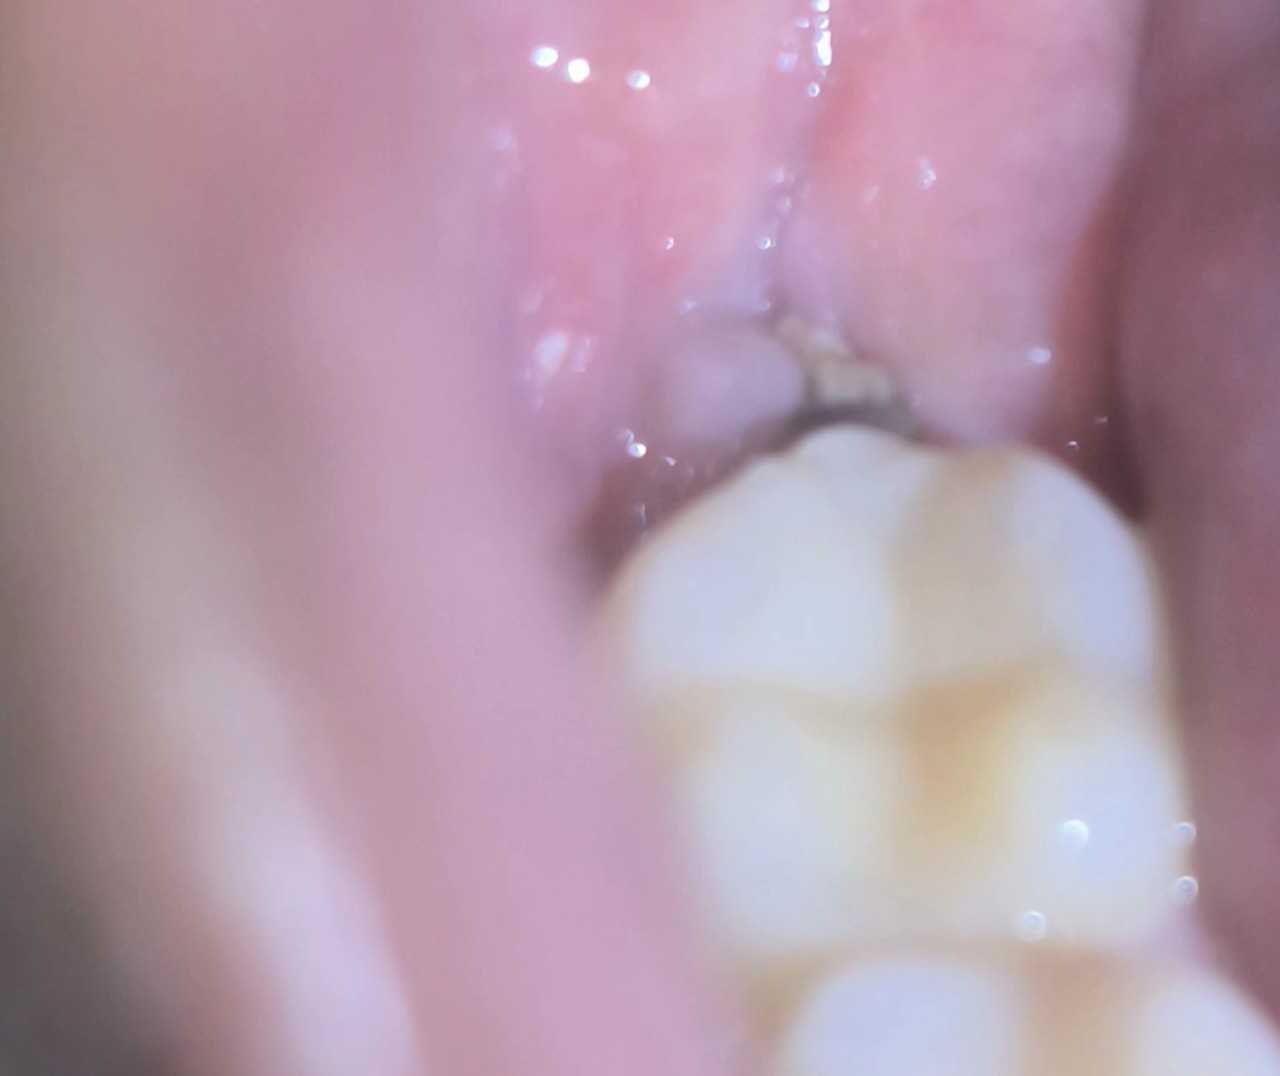

Здравствуйте,2 недели назад удалял 2 зубы мудрости справа, в принципе первую неделю было нормально, уже после 1 дня я не принимал обезбол, а сидел на антибиотиках 7 дней, как велел врач. Но я заметил что-то чёрное в лунках сначала сверху уже на 7-8 дне, но особо не обратил внимание так как сложно было посмотреть внятно и не болело ничего и я просто забил. К 12 дню, я заметил что-то чёрное в нижней лунке, как будто омертвевший ткань или затвердевшийся еда. Я пытался удалить через ирригатор на маленьком напоре, но как будто я повредил красную ткань, но ничего не болит, отеков вообще нет, как и вони. Дальше проверять тоже не стал. А теперь вопросы

А ещё хотел бы сказать, что я пренебрегал ванночками после еды уже после недели, может быть реально еда или что-то в этом роде которая затвердела, снизу предоставлю фотографии, то что мутно это верхняя лунка, камера не смогла нормально фокус дать

"2) Что-то черное это не опасно и смоется ли оно само через время, " - Ничего опасного на фото я не увидел. Да, возможно пищевые остатки.

"но ничего не болит, отеков вообще нет, как и вони" - Вот три симптома, на которые вы должны ориентироваться.

Я повода для волнения не увидел.